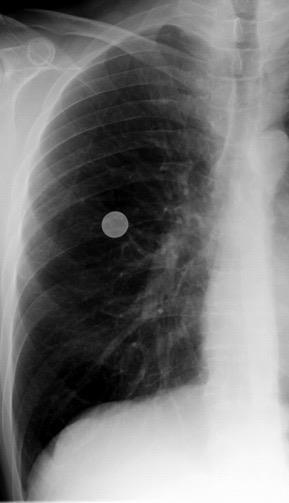

Nódulo en língula.

Cirugía de Ca .de mama hace 23 añosedema de brazo y ganglio en axila. ¡Metástasis!.

Ecanow JS et l. Axillary Staging of Breast Cancer: What the Radiologist Should Know. Radiographics 2013